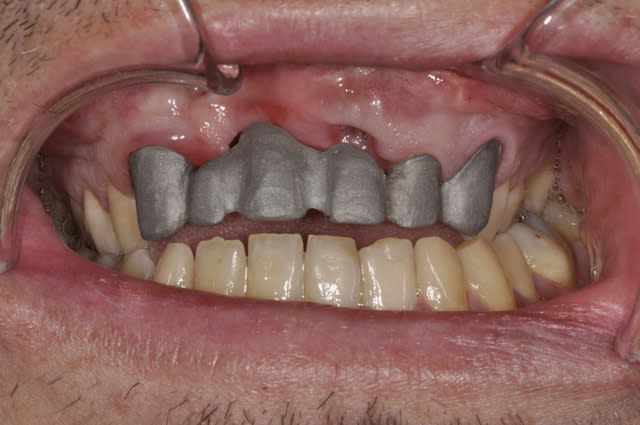

si,

l'armature metallique ne sert que pour l'essayage et après elle est dupliquée en armature zircone et enfin montage du cosmetique.